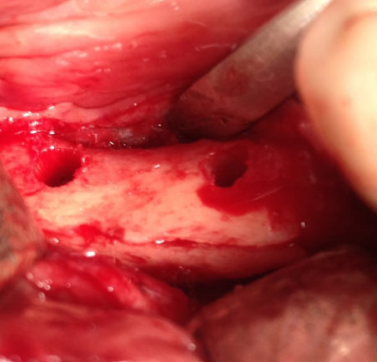

El injerto en bloque obtenido se dividió con la ayuda de un disco de corte en dos láminas corticales de 1,5 mm (Figura 4). Seguidamente, se fijó una de las láminas en la parte coronal del defecto óseo, creando un espacio virtual en altura de aproximadamente 6 mm que se rellenó con las partículas de hueso autógeno obtenidas (Figura 5). La lámina remanente se posicionó y fijó conformando la pared vestibular del defecto (Figura 6). La sutura se llevó a cabo mediante puntos de colchonero, favoreciendo así la cicatrización, y se utilizó monofilamento de 5/0. El CBCT postquirúrgico de control mostró una correcta reconstrucción tridimensional del defecto y el postoperatorio cursó con normalidad, sin signos infecciosos ni dehiscencias de la herida y sin alteraciones sensitivas (Figura 7).